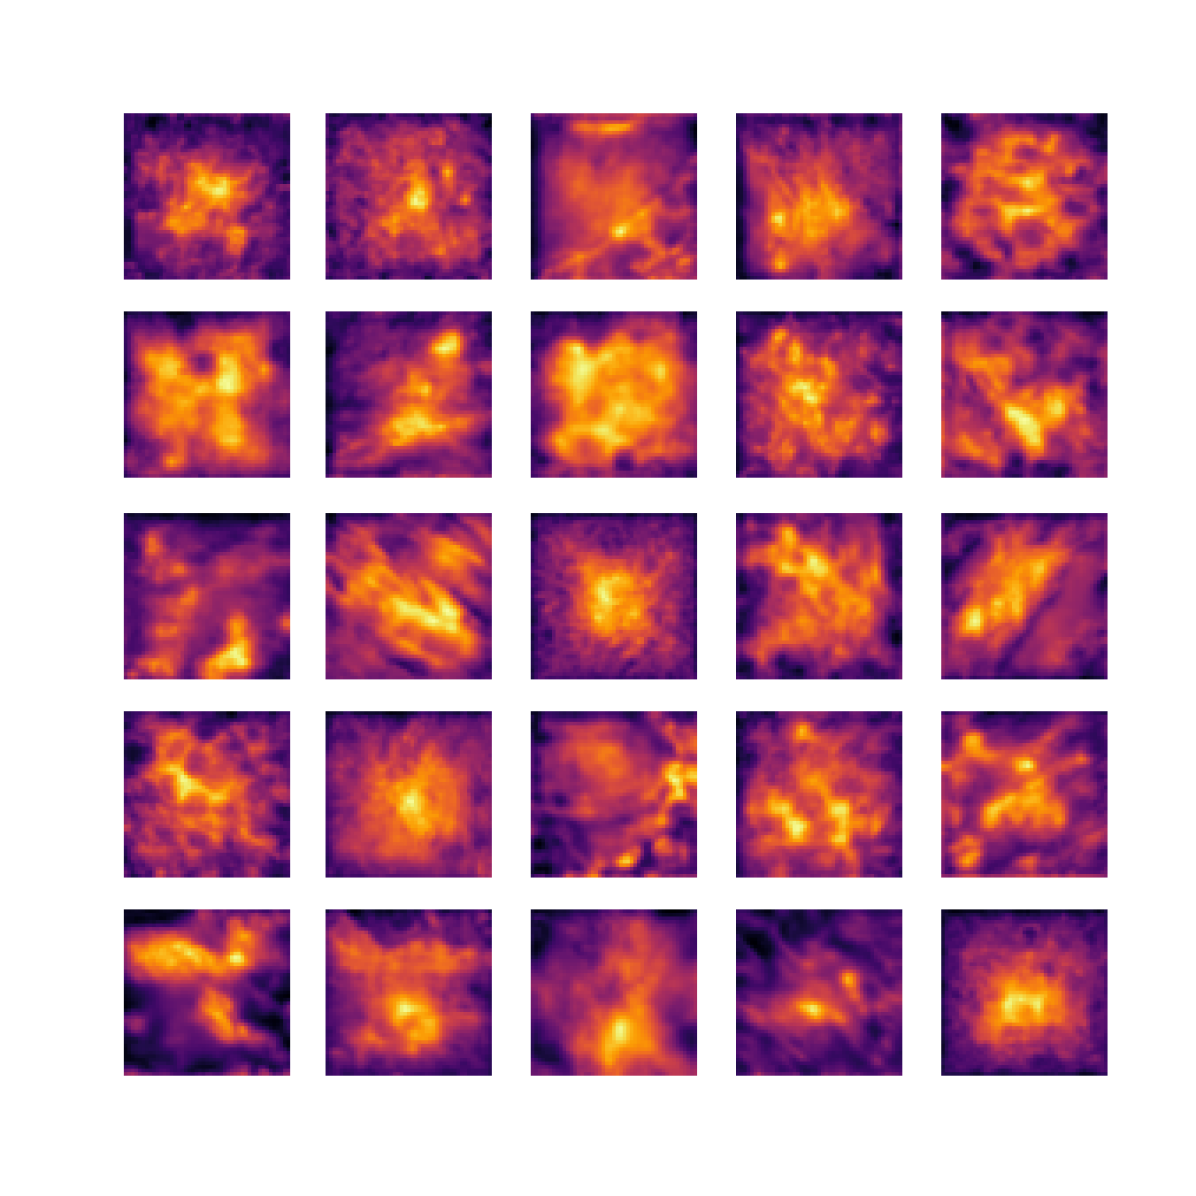

We also analyse the activation maps for each model using GradCAM as described in section S3. This offers more insight into the areas of the image which are contributing most heavily to the models’ representations. In Figure 4(b) we present some representative examples, however, a larger selection which was chosen at random is presented in Figures S10 to S25. The larger selection makes it easier to see the emergent patterns, including that privileged Siamese models tend to mainly identify features which are strongly present in both inputs, while unprivileged Siamese models tend to learn more diffuse features that are not specific to one cell phenotype or image region. TriDeNT ♆ incorporates both sets of features, learning both features specific to the privileged data and more the general features associated with unprivileged Siamese networks.

We can see in Figure 4(b) panel A that for ERG, the privileged Siamese model focuses almost exclusively on any nuclei which could be endothelial cells. As there are very few endothelial cells in the dataset, it could be an effective strategy to identify anything that could potentially be an endothelial cell to minimise the difference between the representations of the H&E model and the IF mask model. In the corresponding unprivileged Siamese image, we see that the model identifies some of these nuclei, albeit less strongly, but also focuses heavily on the other tissue and even the background, while strongly fixating on two spots of debris in the center of the image. This model has less ‘incentive’ to learn the weak features related to endothelial cells as these occur rarely and are not easy to detect, while more generic strong features such as the presence of connective tissue and the prevalence of background are more common and predictable from augmented images. We see that TriDeNT ♆ combines these two feature sets, strongly identifying nuclei while also identifying the connective tissue.

In panel C we see a similar pattern, with the privileged Siamese model fixating solely on the nuclei, while the TriDeNT ♆ model takes a more balanced approach. The unprivileged Siamese model appears to focus on a single cluster of nuclei while neglecting others, and similarly identifies an area of fibroblasts with its distinctive pattern but does not others.

In contrast to panels A and C which represent models with poor privileged Siamese results, panels B and D represent models whose privileged Siamese results were comparable to both TriDeNT ♆ and even the supervised baseline. It is therefore interesting to note that there are far more similarities between the privileged Siamese and TriDeNT ♆ models in both cases. Particularly in panel B, TriDeNT ♆ and the privileged Siamese model return virtually identical heatmaps, with both strongly identifying epithelial nuclei and neglecting the same areas of connective tissue. The unprivileged model in this case appears to focus solely on the centre of the image, giving a significantly different heatmap to the other panels.

Panel D again shows the previous pattern, with the privileged Siamese model identifying the features strongly present in the privileged data – fibroblasts – while neglecting the nuclei present. TriDeNT ♆ also strongly identifies the connective tissue, but, unlike the privileged Siamese model, does not completely neglect the nuclei. The unprivileged Siamese model primarily identifies background, and does not appear to identify the nuclei in this example.